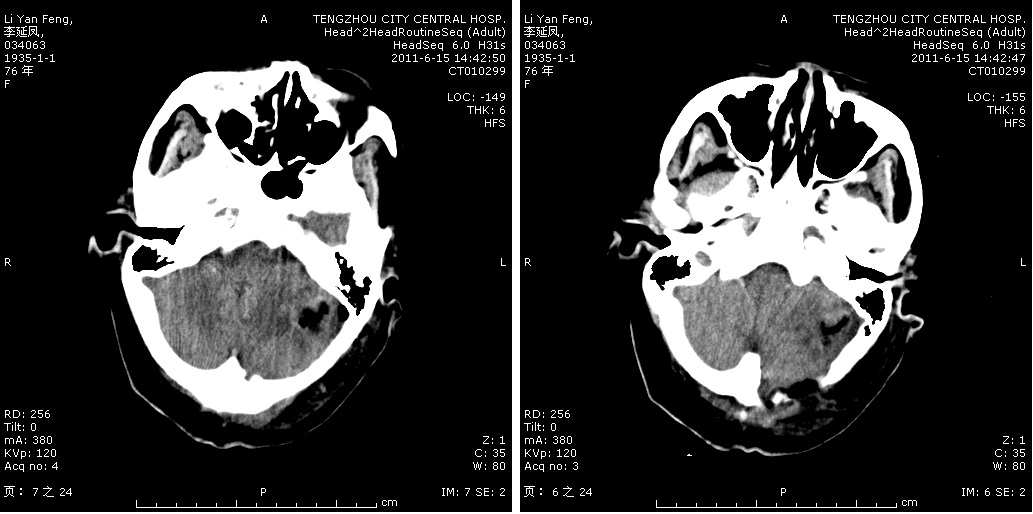

三叉神經(jīng)微血管減壓手術(shù)切口

術(shù)中顯微鏡鏡下神經(jīng)顯露

椎管內(nèi)腫瘤 椎管內(nèi)腫瘤術(shù)中